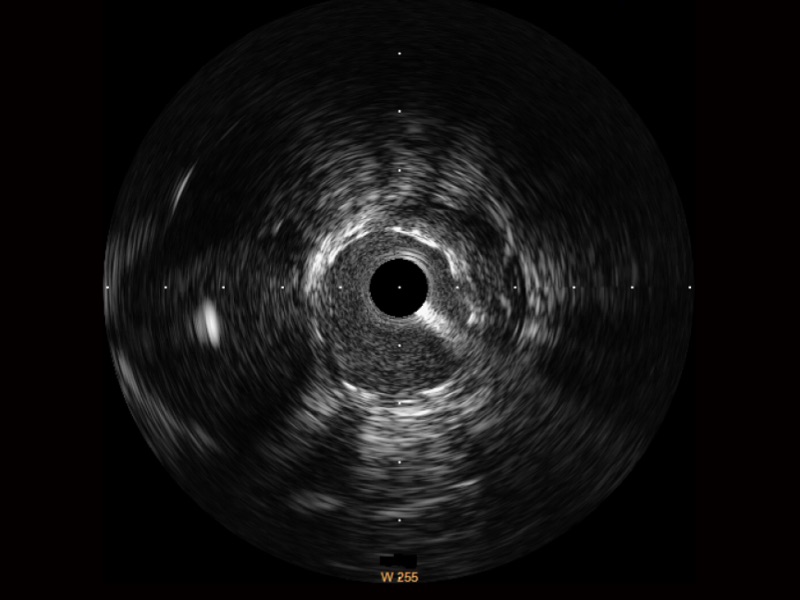

• 16877太阳集团宽频IVUS图像

对比传统IVUS导管成像,16877太阳集团宽频IVUS图像的近场支架梁显影更细腻,远场中膜外血管仍清晰可辨,兼顾远中近,兼顾分辨力与穿透深度